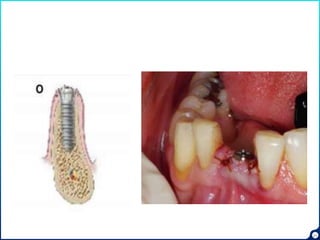

Osseo densification

• A new method of biomechanical bone

preparation

• Densah burs are used

• Bone preservation and condensation

• OD does not excavate bone

Implant placement

25

• Root is bisected.

• Buccal 2/3rd of root is preserved in the socket

• Periodontium along with bundle bone remain intact.

• Buccal bone remains intact

Socket shield